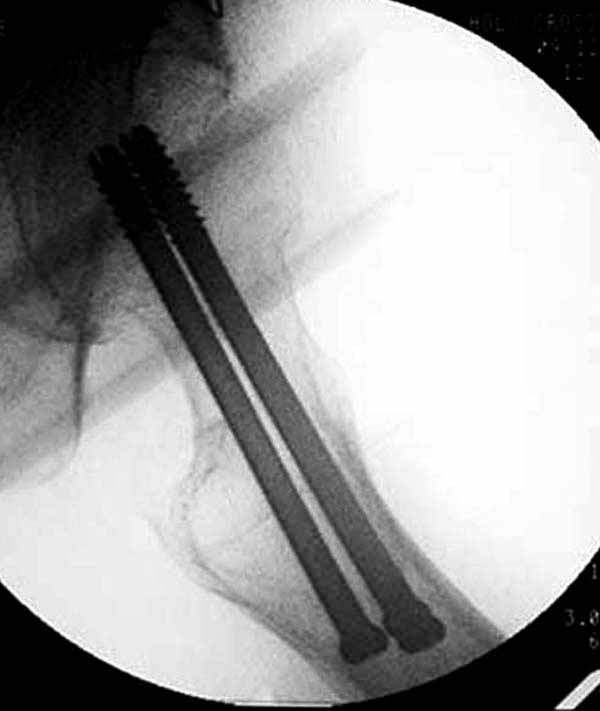

Как отметили коллеги, необходимо обратить внимание на последовательность введения каннюлированных шурупов. Рекомендуется введение в форме “V”, т.е основанием вниз, потому что в другой последовательности за счет увеличения стресса латерального кортекса имеется риск перелома. За редким исключением удается установить Guide wire с первой попытки и многоразовые пробы спицей увеличивают стресс. Небольшая травма может привести к перелому.

Здесь подобный случай, где стрессовый перелом обнаружен через 2 недели после фиксации. Применен Blade Plate с дополнительными шурупами.